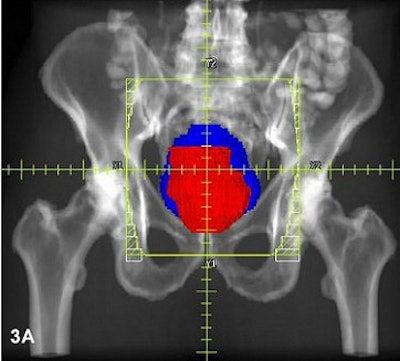

Three radiation fields (PA with right and left lateral) were used for all patients, using CT-based 3-D treatment planning. Rectum is red; bladder is blue.